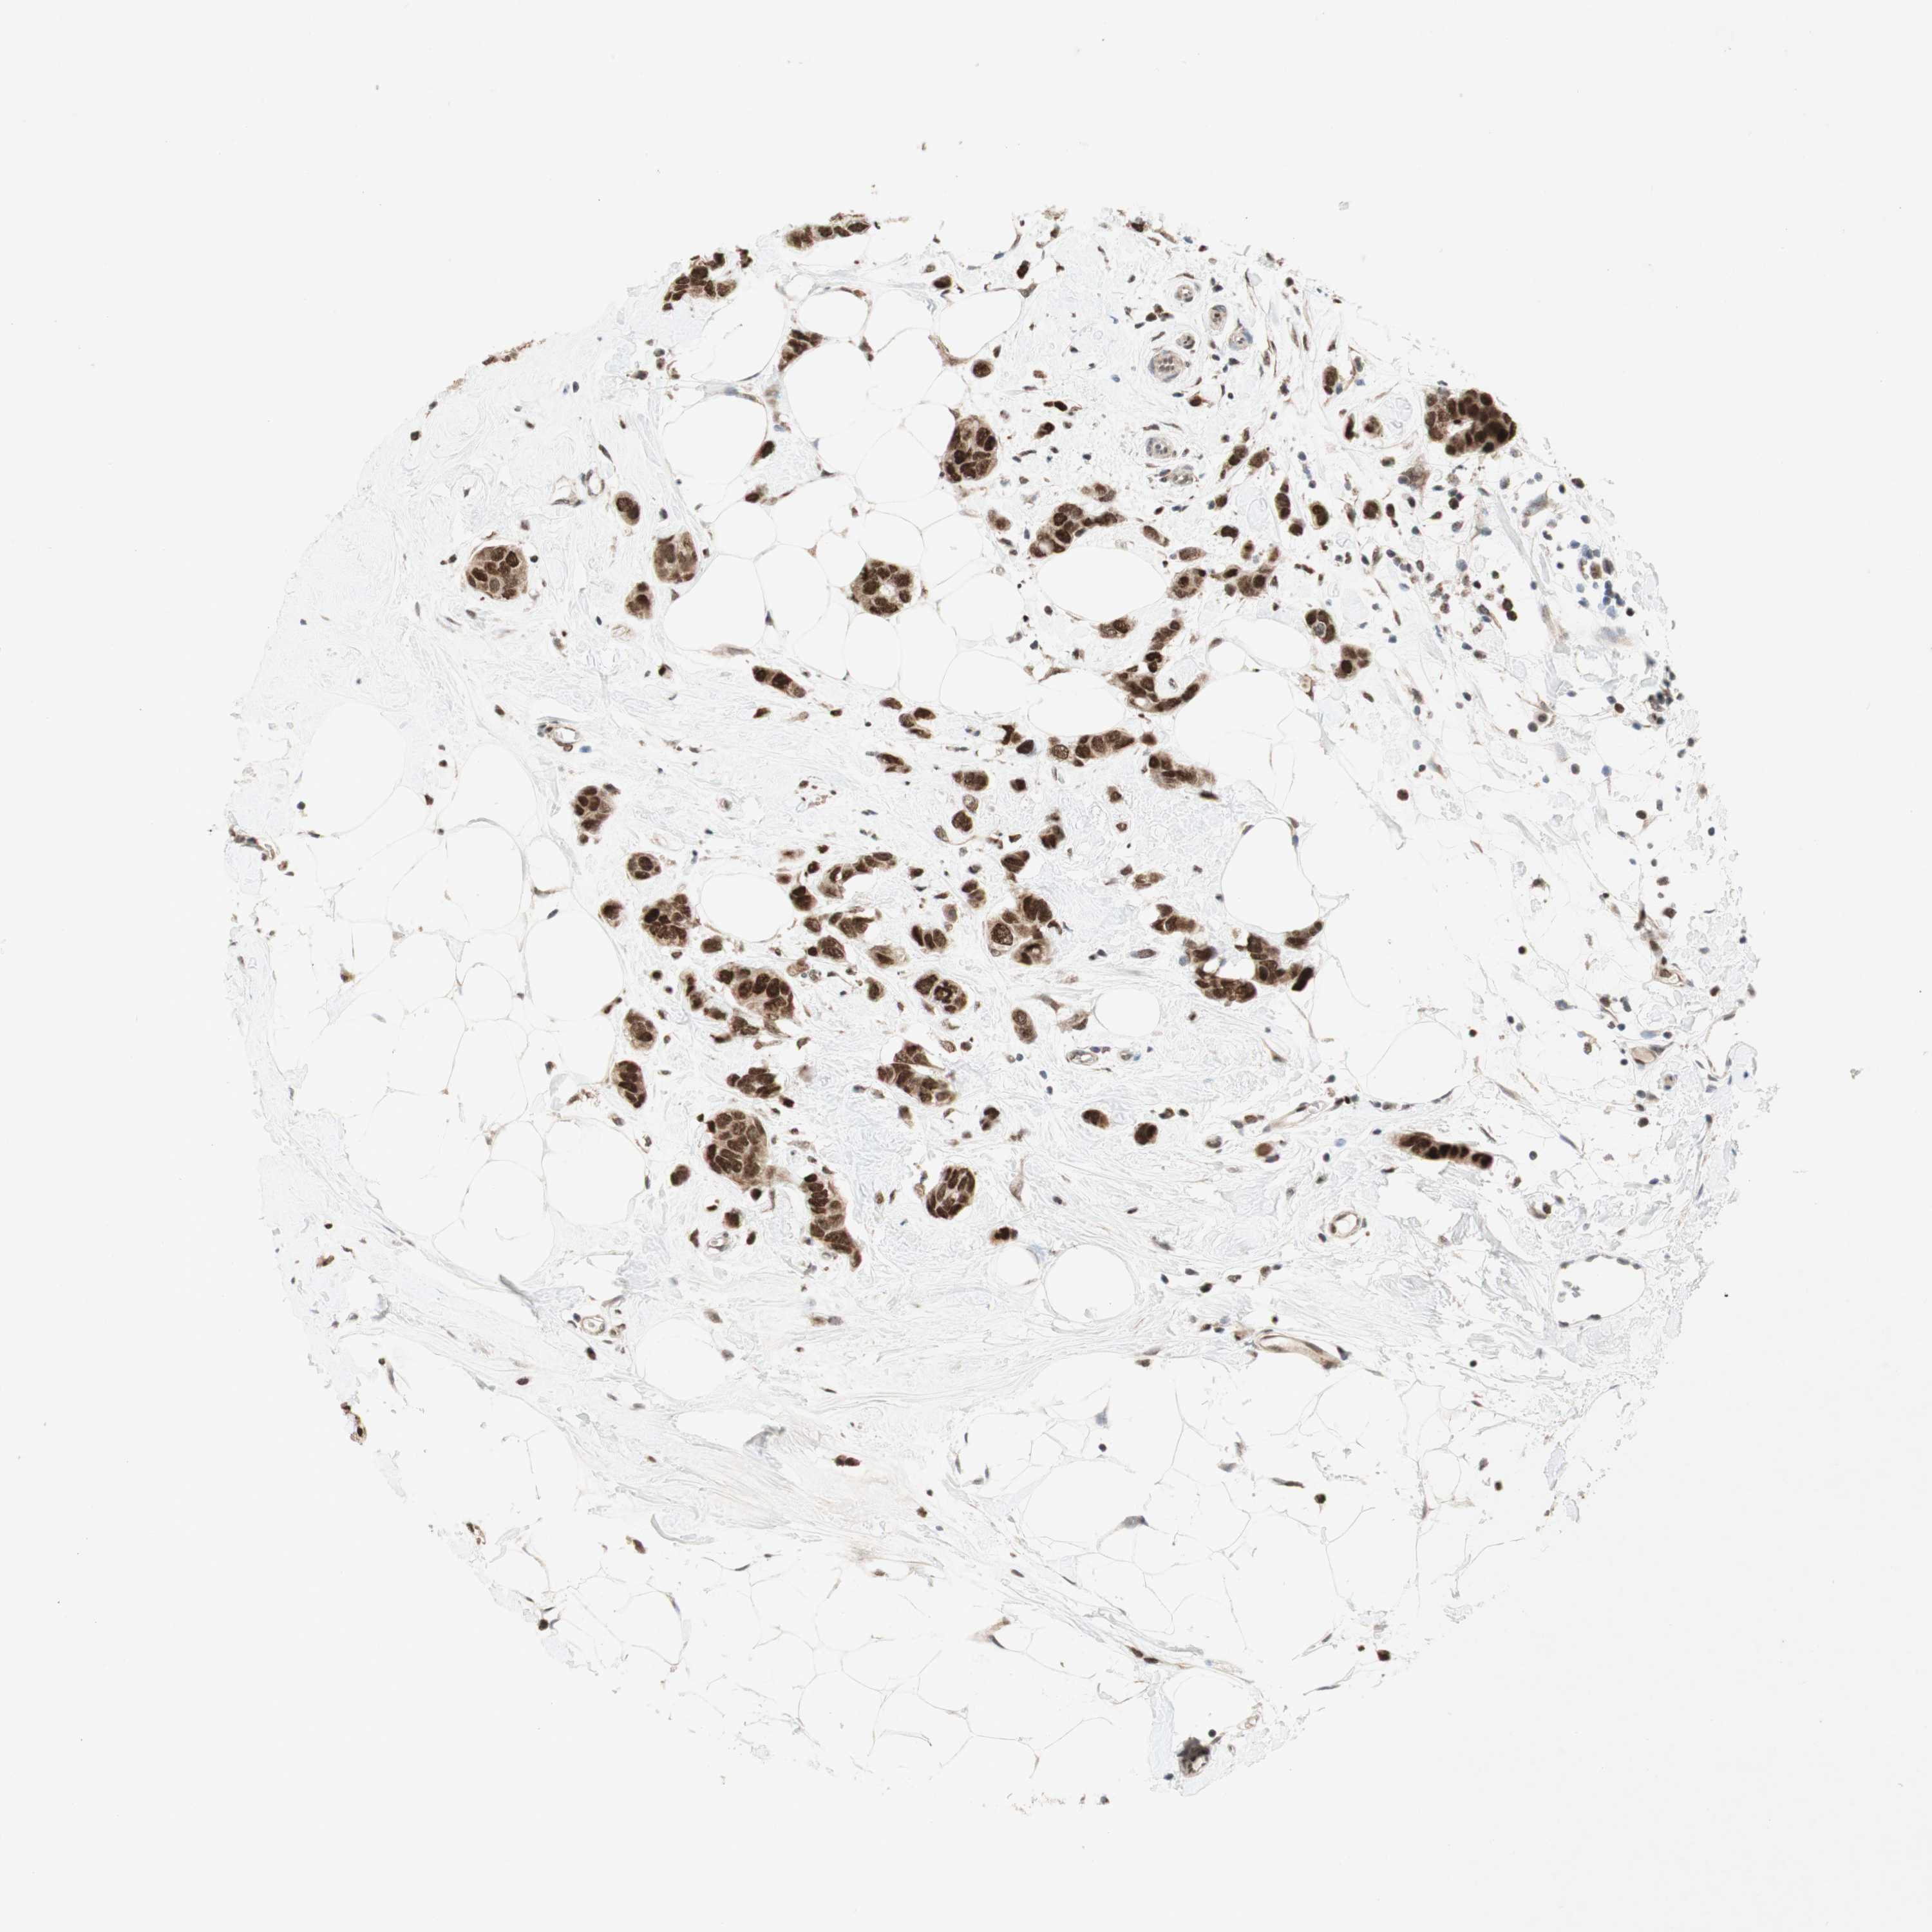

BRCA TCGA BRCA VALIDATION PROTEIN EXPRESSION

Breast cancer

Human cancer